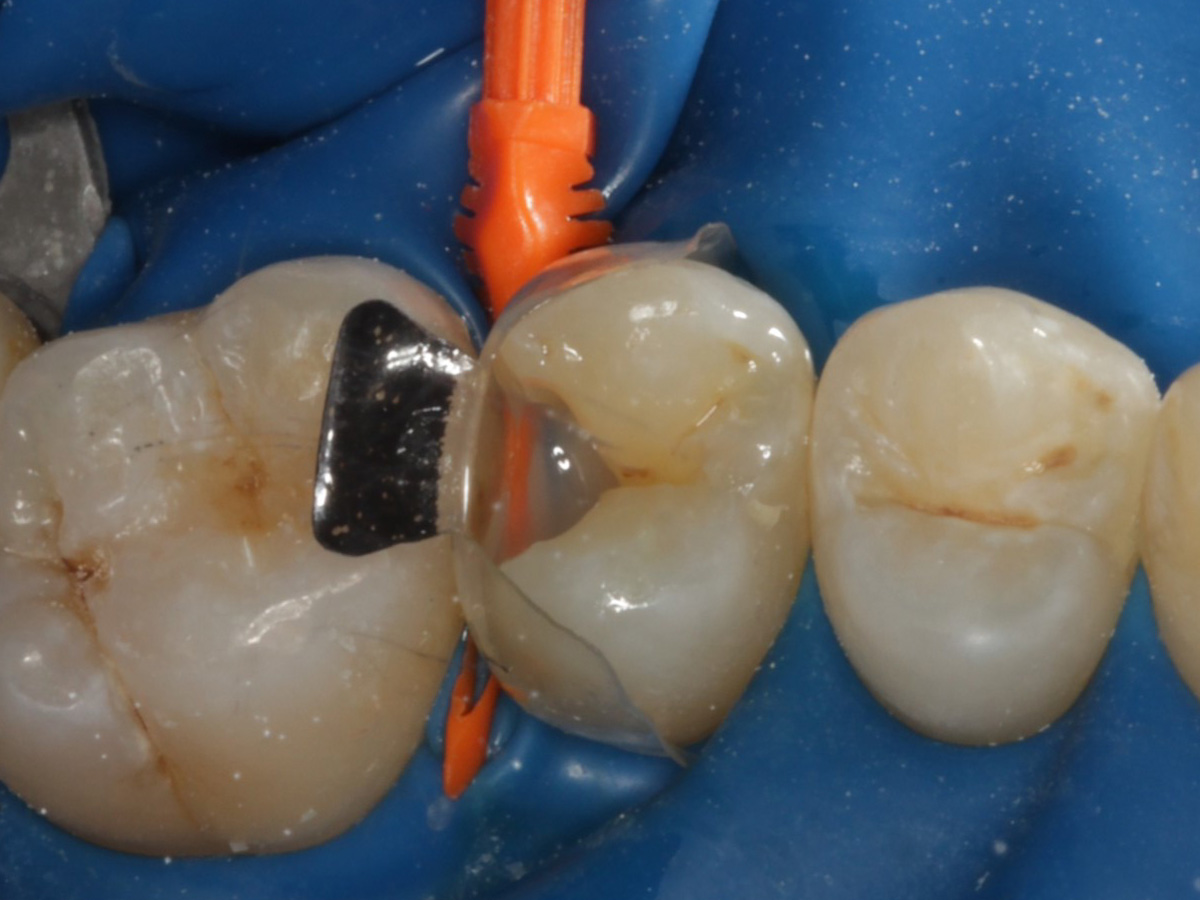

Abbildung 1

Approximalraumkaries an Zahn 25 distal

Abbildung 5

Defektdarstellung

Nach Applikation der Matrize: Evolve Schwarz Prämolar- 7 mm; Schmelzätzung